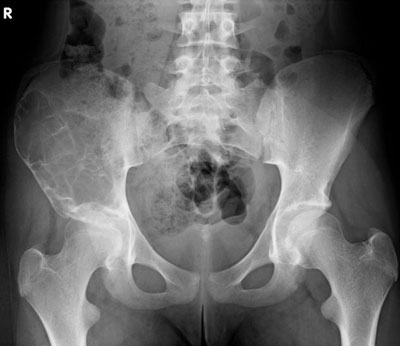

Die Röntgenuntersuchung von Becken/Hüfte zeigt eine septierte geographische Osteolyse in der Ala und im Korpus des Os Iliums rechts. Das Röntgenbild und die Aufnahmen der nachfolgenden MRI-Untersuchung sehen Sie hier: